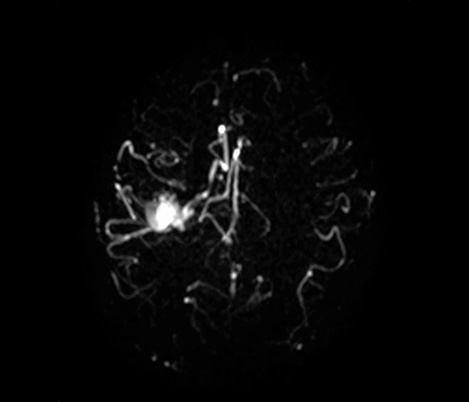

70% of radiologists consider neuro indications to be challenging, mostly due to a lack of appropriate imaging and visualization techniques¹. Philips aims to provide the best possible diagnostic clarity and treatment guidance for all patients with neurological disorders. By leveraging our dStream digital platform, this year, we are introducing, a set of novel imaging and visualization strategies. These may empower you to resolve complex neuro questions with more certainty, as well as unlock new neuro territories in advanced Neurofunctional applications. This is a key step towards elevating neuro diagnostics and ultimately touching more lives with MR imaging. ¹ TMTG Market Survey 2016

Clinical cases from nearly every anatomy Explore 100+ clinical cases from your peers around the globe, that showcase how Philips MR digital technology strengthens your imaging needs.

Learn about technical background, protocol optimization strategies, imaging pitfalls and future directions.